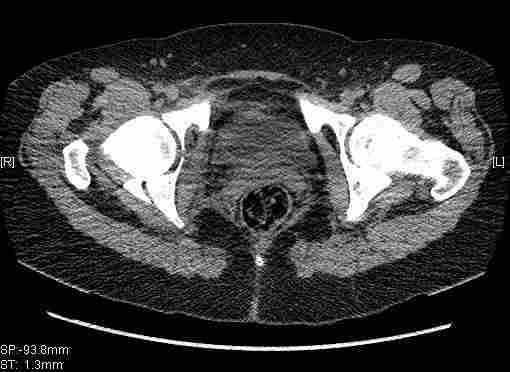

Удалось сегодня вывести пациентку в соседнюю больницу, где есть кт. Срезы сделаны только горизонтальные.